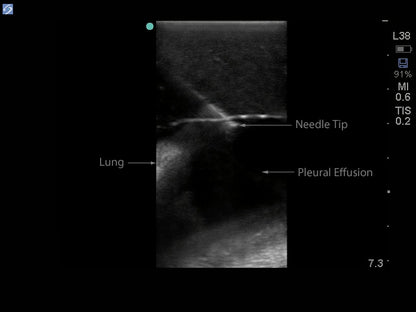

This model is excellent for assisting clinicians in gaining proficiency in using ultrasound to identify and guide needle and small gauge catheter insertions in a patient with pleural effusions for diagnostic and/or therapeutic purposes. This ultrasound tissue insert module contains all of the structures to efficiently and effectively learn how to utilize ultrasound for guiding midscapular thoracentesis procedures including; the chest wall superficial tissue, 6th, 7th, 8th, and 9th ribs and intercostal spaces, pleural cavity with lung and atelectatic lung, diaphragm, and superior spleen segment. The pleural fluid collections allow users to develop and refine their ultrasound guided thoracentesis skills.

- The ultrasound tissue insert offers extremely realistic sonographic imaging characteristics and is designed for guiding the placement of needles and small catheters (18-21 gauge needles and associated catheter kits). Positive fluid flow offers users feedback when pleural effusions are accurately accessed. The fluid is easily refilled using a quick fill luer lock or can be connected to an IV reservoir for continuous fluid delivery.

- Superb ultrasound imaging characteristics: extremely realistic in ultrasound imaging characteristics and feels like real human tissue

- Ultrasound tissues match the acoustic characteristics of real human tissue so when you use your ultrasound system on our training models, you experience the same quality you expect from imaging patients in a clinical environment